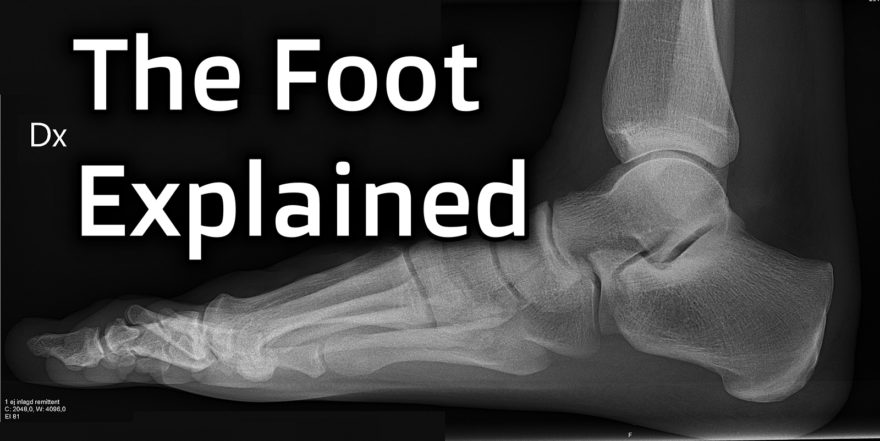

Below is a picture of a bunion:

and here is what it looks like if you were to zoom in to the bones:

Photo credit: Mikael Häggström, M.D.